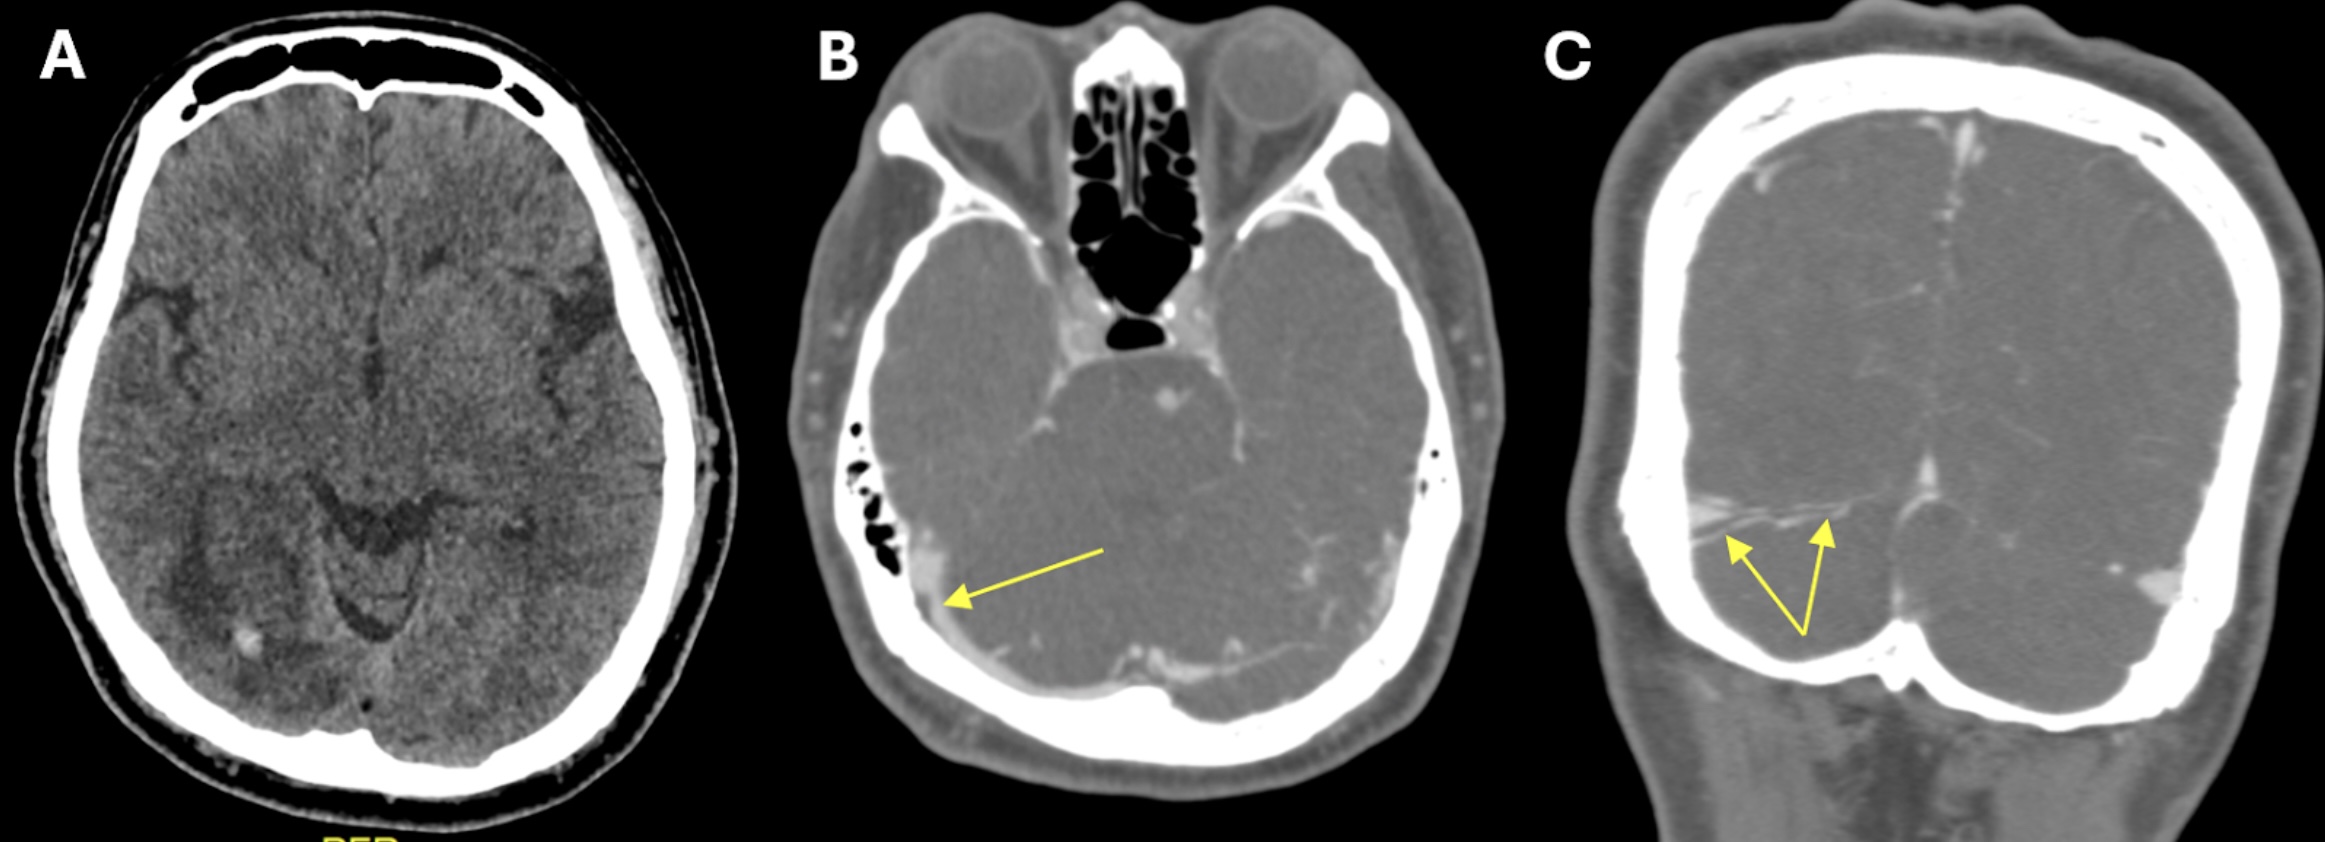

The current COVID-19 pandemic has prompted the development of vaccines to control the spread and severity of SARS-CoV-2. However, there are growing reports of different types of strokes, including ischemic and hemorrhagic strokes, as well as cerebral venous sinus thrombosis (CVST), following COVID-19 vaccination. We presented a case involving a 55-year-old male with a history of ischemic heart disease who exhibited an atypical presentation of visual field impairment one week following Sinovac-CoronaVac COVID-19 vaccination. The patient also experienced mild headache and vomiting for two days preceding the onset of visual symptoms. Right eye’s best-corrected visual acuity was 6/24, and left 6/15. A visual field confrontation test indicated left homonymous hemianopia. An urgent CT venography of the brain documented right transverse sinus thrombosis with occipital haemorrhagic infarct. A nasopharyngeal swab tested negative for SARS-CoV-2, and baseline blood investigations were within normal ranges. The patient was given one week of low-molecular-weight heparin, followed by a three-month course of oral anticoagulant. Post-treatment, there was marginal improvement, although a residual visual field defect persisted. In conclusion, while COVID-19 vaccination remains essential, clinicians must remain vigilant for rare adverse events like CVST and be prepared to manage these cases promptly to ensure patient safety.